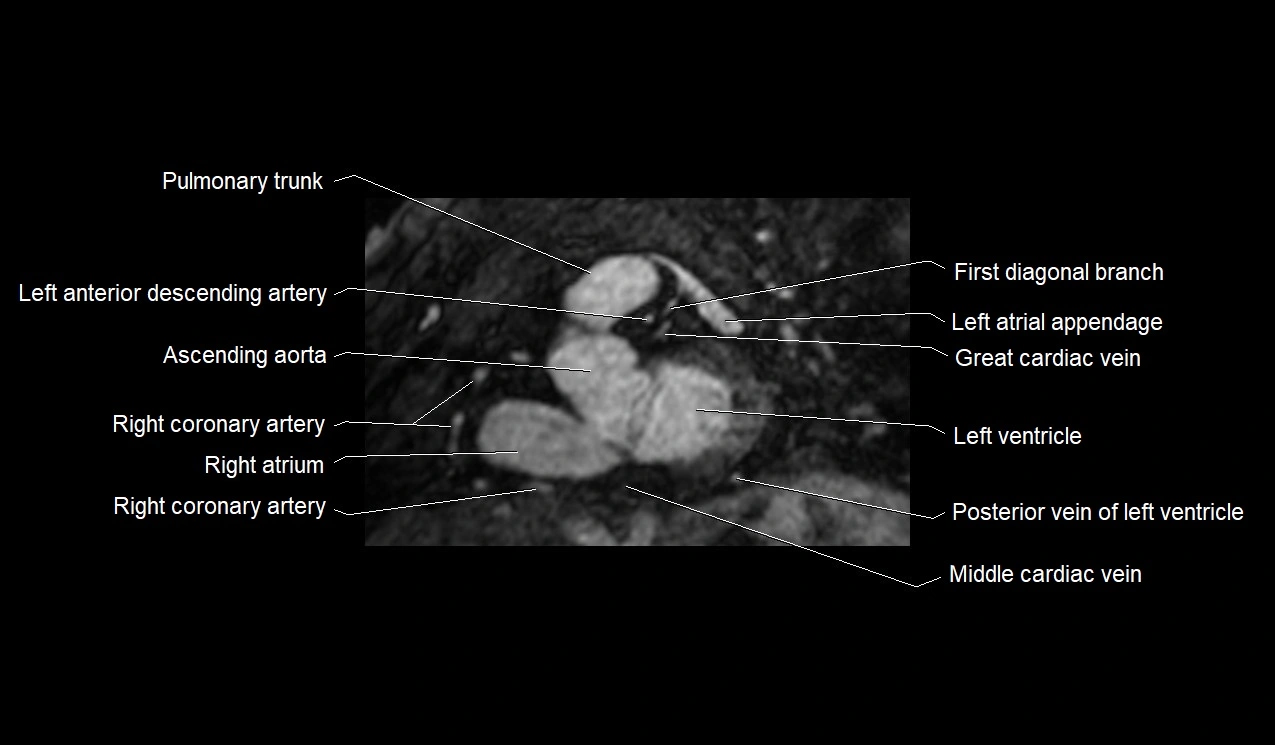

MRI image